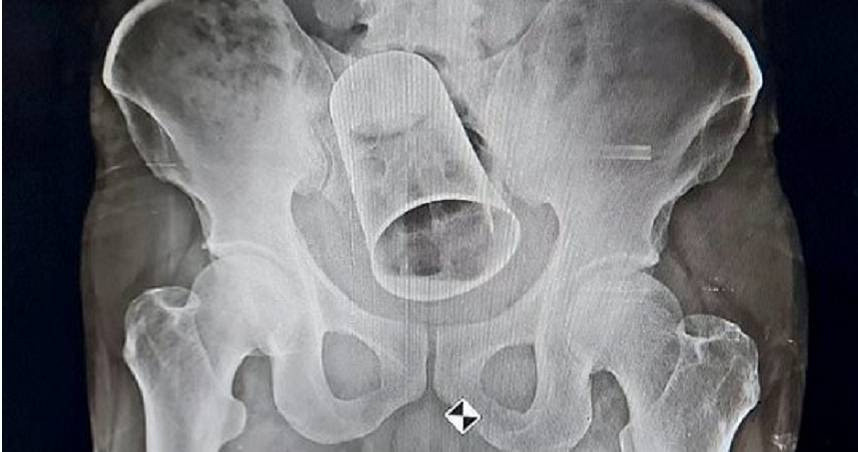

| Say rượu, người đàn ông bị bạn chơi khăm suýt hỏng hậu môn. |